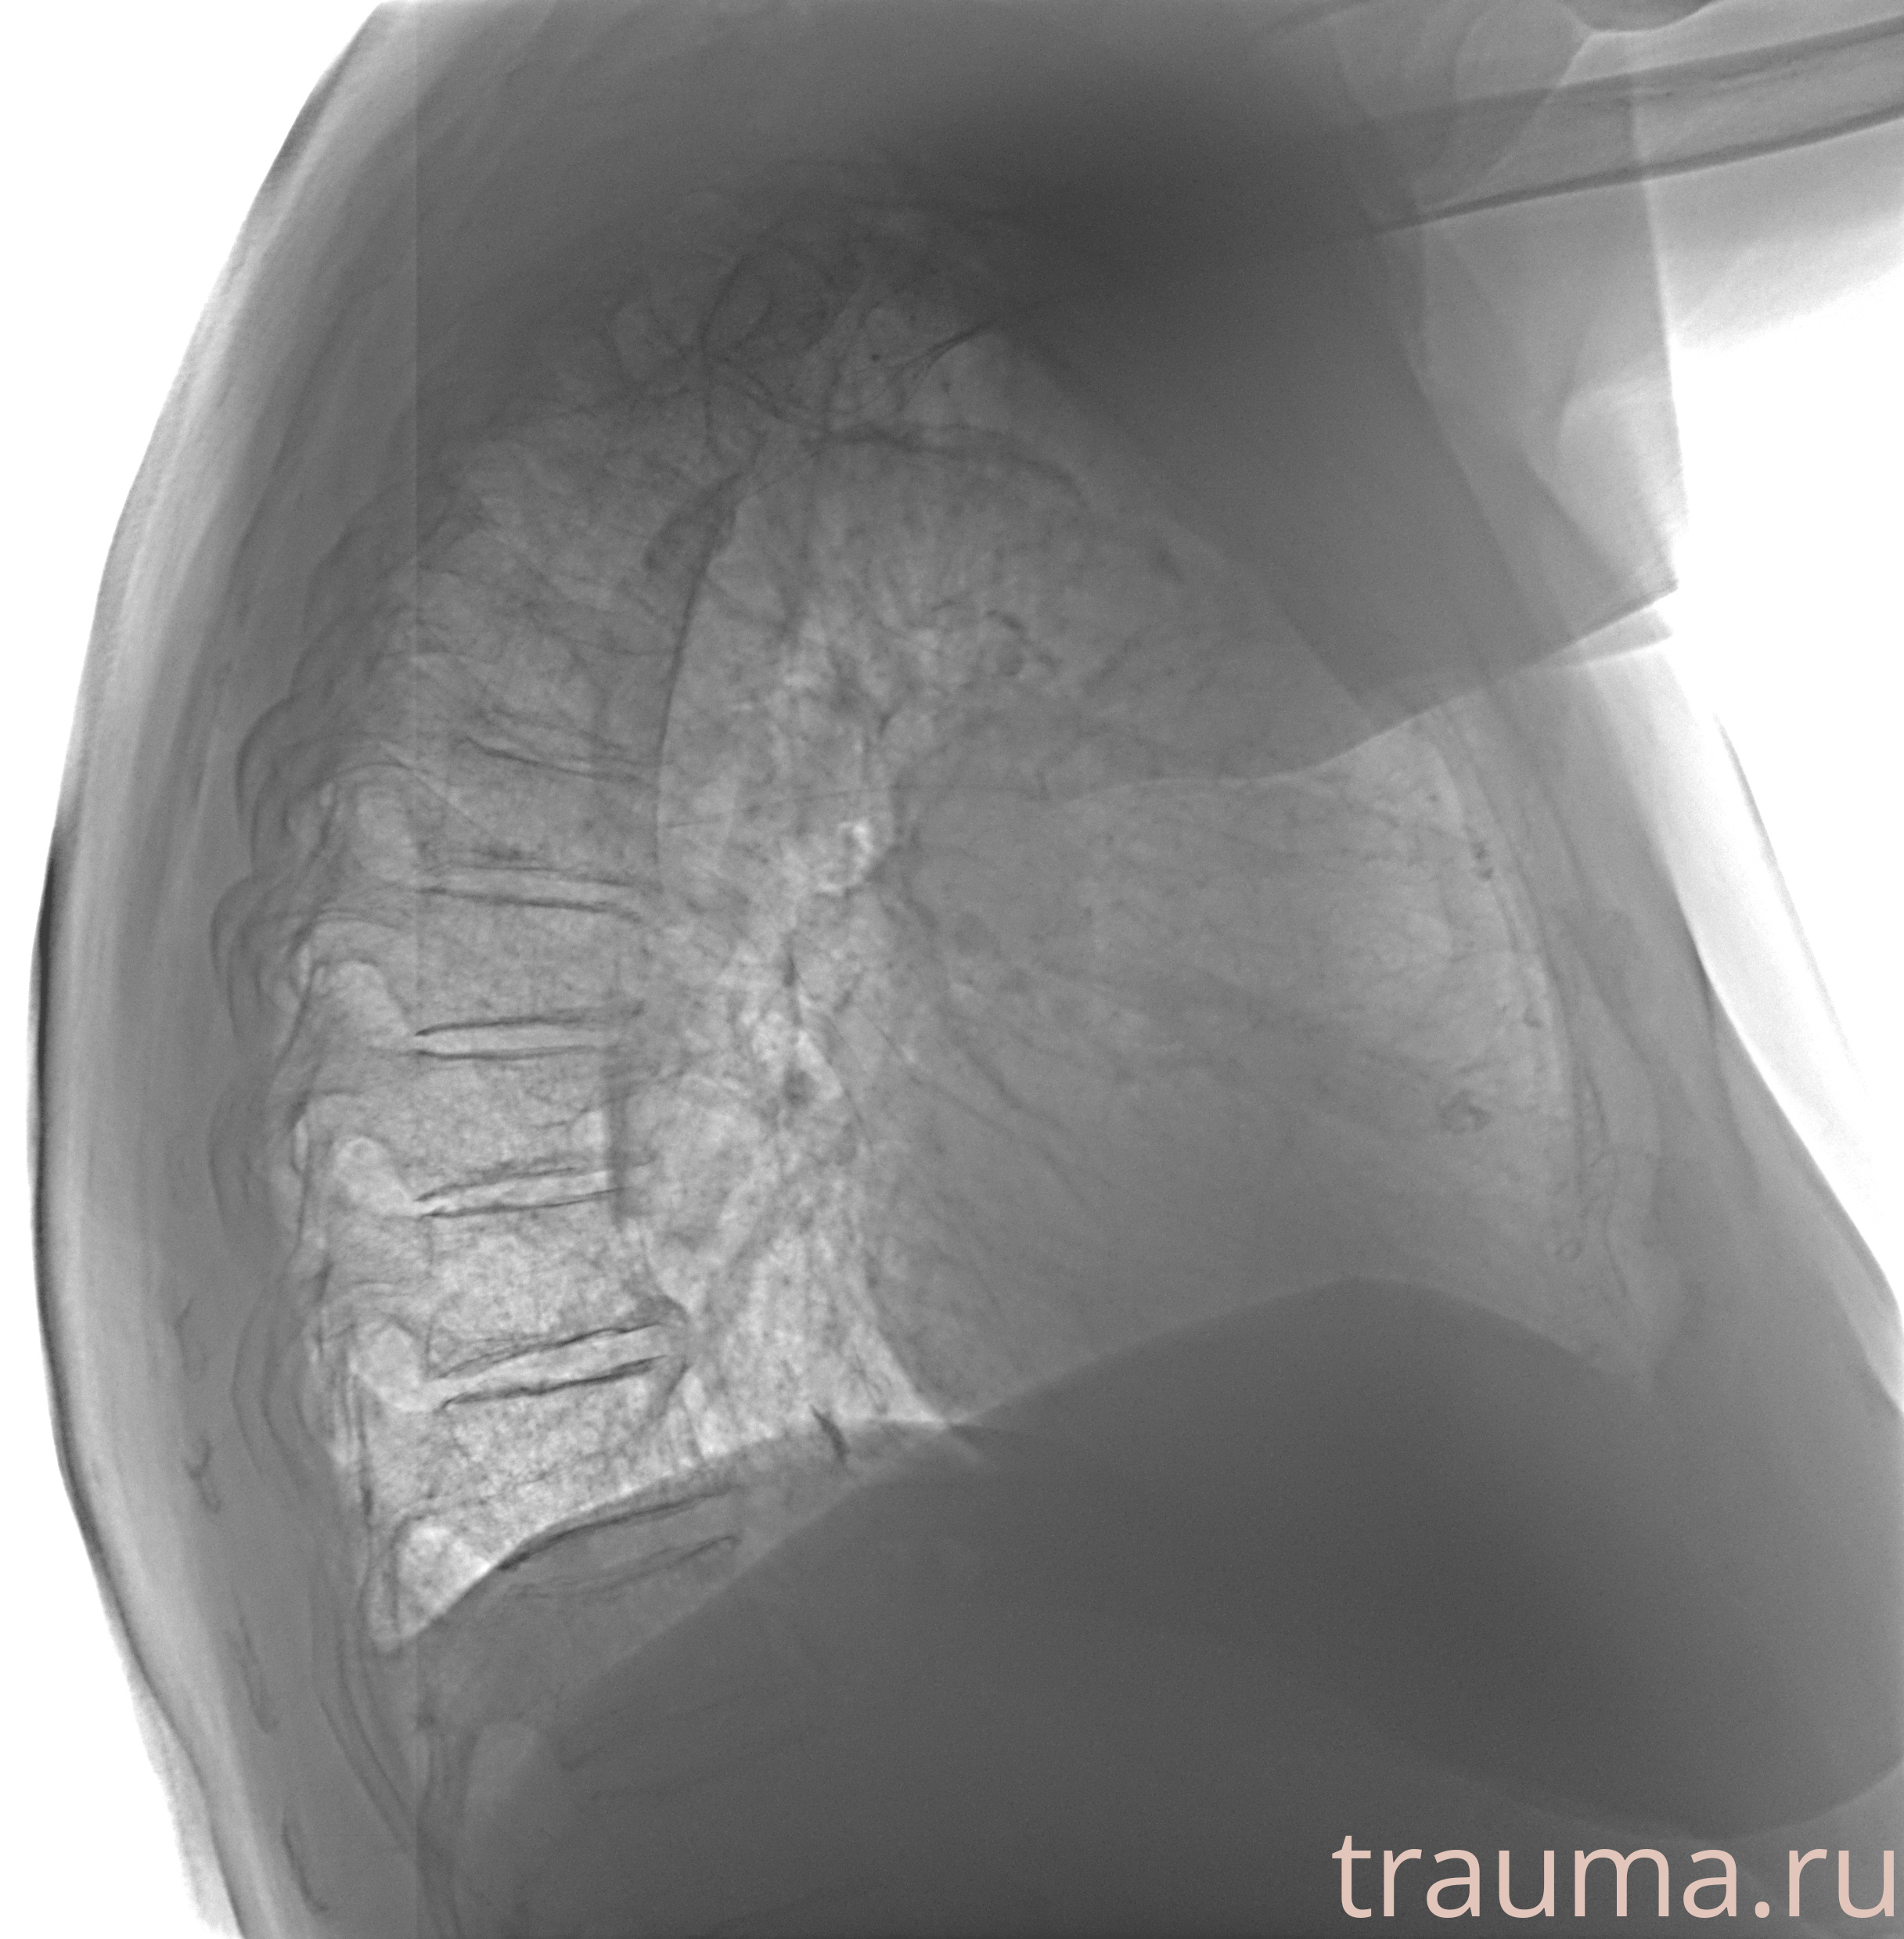

Рентген на дому: по вашему адресу приезжает врач-рентгенолог, травматолог-ортопед с мобильным рентгеновским аппаратом, проводит диагностику травмы или заболевания, делает необходимые рентгенограммы, дает рекомендации по дальнейшему лечению. Получить качественные снимки в домашних условиях возможно благодаря уникальной методике, разработанной МосРентген Центром для института  Склифосовского